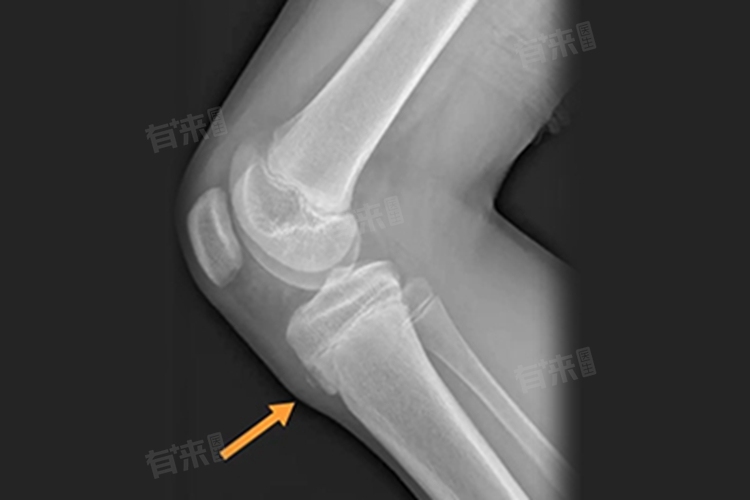

1、炎症位置特点:胫骨结节是髌韧带附着处,炎症主要局限于此,与负责长高的骨骺区域相对独立,炎症通常不会扩散至骨骺,所以对长高的直接影响较小。

3、病情严重情况:若胫骨结节炎长期未愈,炎症持续刺激周围组织,可能影响局部血液循环。而骨骼生长需要良好血运提供营养,极端情况下,可能间接对骨骼发育产生轻微影响。